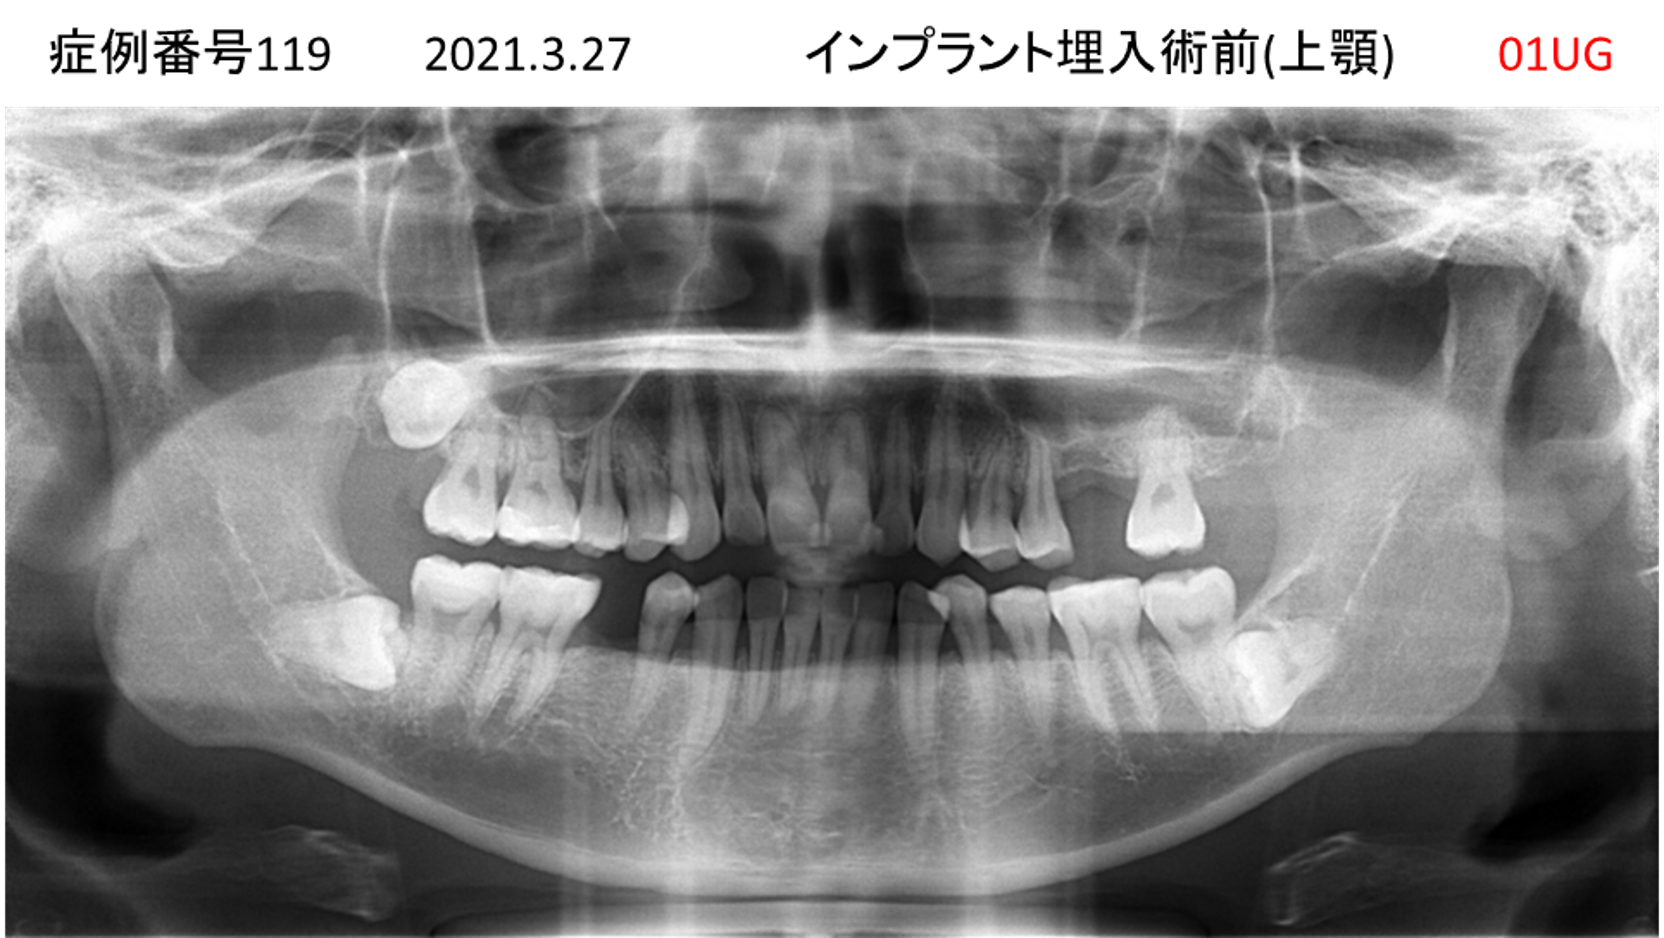

上の前歯が揺れてきてかめない患者様のインプラント症例

| 治療名称 |

インプラント |

| 治療費用 |

335万円+税 |

| 治療期間 |

4か月 |

| 患者さんの症状(主訴) |

上の前歯が揺れてきて噛めない |

| 治療内容 |

サイナスリフト 抜歯即時インプラント |

| 治療結果 |

ちゃんと噛めるようになった。不安がなくなった。見た目がとても良くなったのすごくうれしい。 |

| 治療の注意点(リスク/副作用) |

インプラントが壊れたら再治療が必要 |